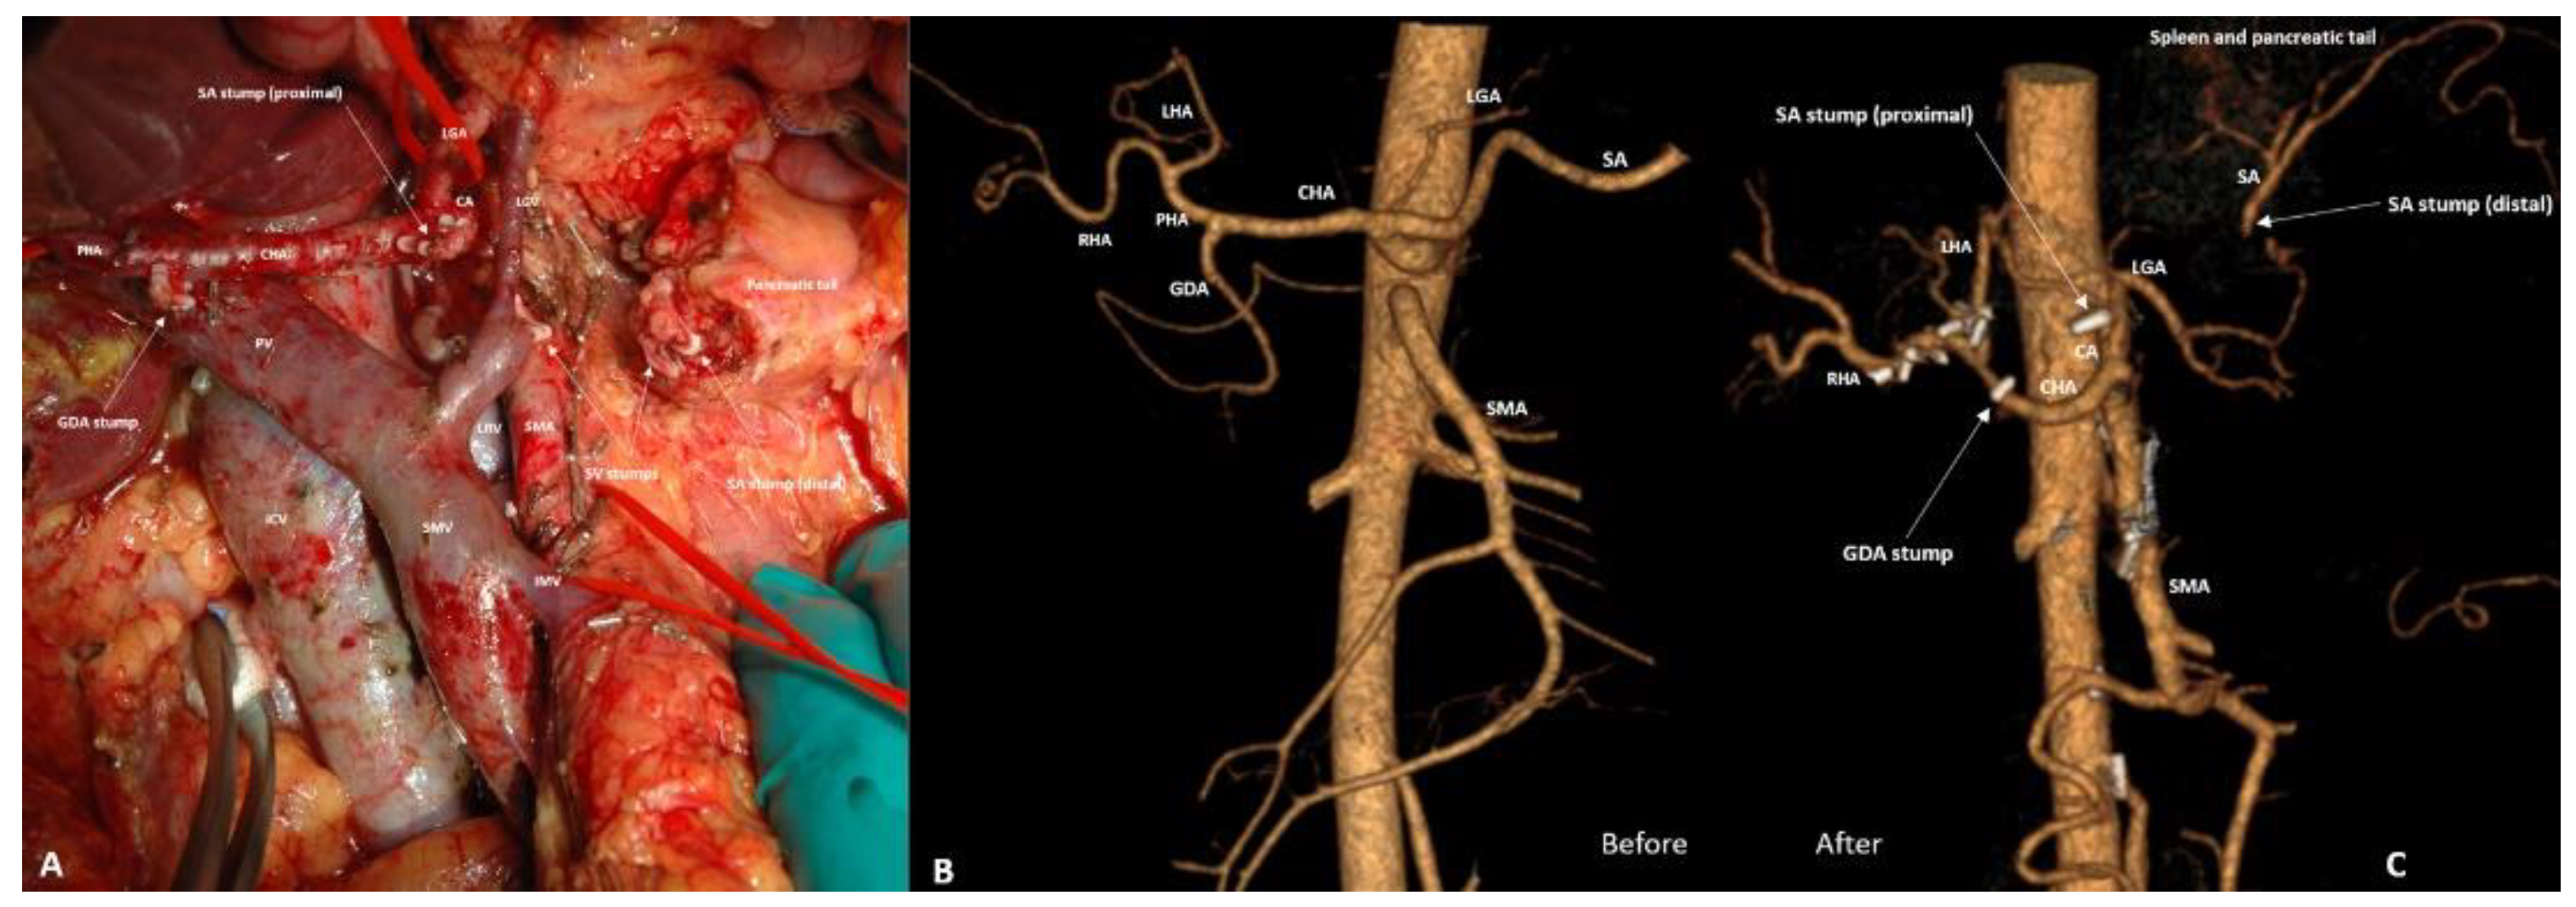

3.4. Spleen-Preserving Pancreatectomies with Resection of the Splenic Artery (Vessels) for Border Line Resectable and Locally Advanced Pancreatic Head Cancers